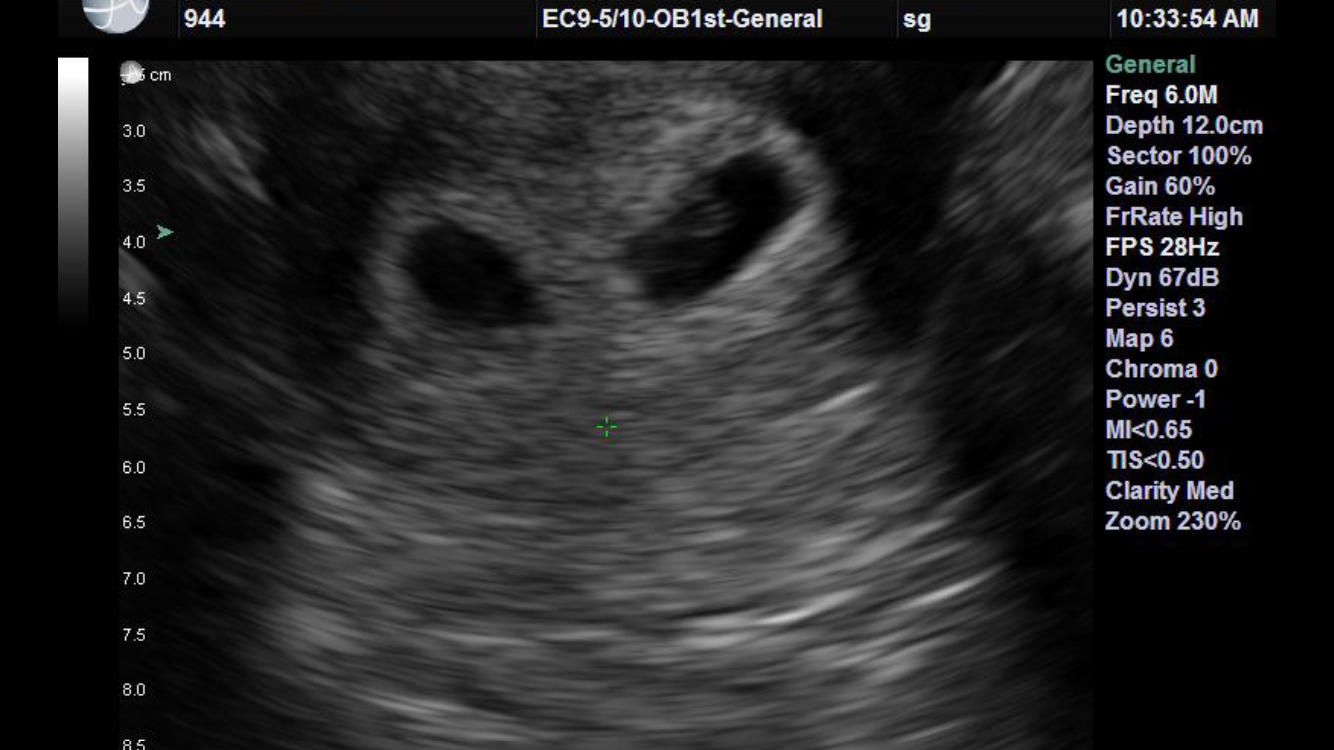

8w6d! Transvaginal. He/she was a little wiggle worm when the Dr first turned the machine on